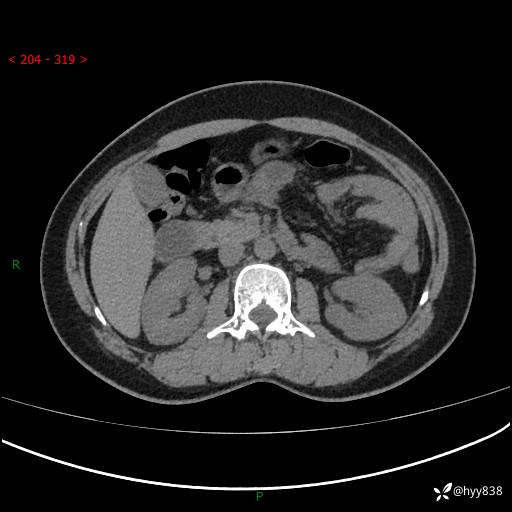

51岁/女,腹痛腹胀1天。白班偶遇,收藏教学备用---(公布详细手术过程)

现病史:患者1天前无明显诱因下出现左上腹部及腰背部胀痛不适,阵发性加剧,伴肛门停止排气;无发热,无恶心呕吐,无畏寒发热,无心慌气短等不适,于当地市第二人民医院就诊,行腹部ct检查提示左上腹区肠系膜血管从剧聚集,分布紊乱伴肠管局限性稍扩张积液,不完全性肠梗阻;考虑子宫颈纳氏囊肿,双侧附件区囊状灶;予以抗炎及对症支持等治疗后未见明显缓解,现患者为求进一步治疗来我院急诊就诊,遂以“肠梗阻”收住入院。 病来,神志清,精神可,饮食睡眠不佳,经灌肠后排便2次,小便正常,体力体重无明显变化。

上腹部CT平扫